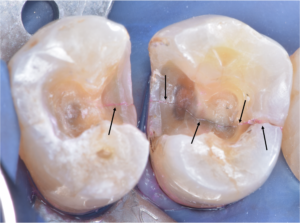

そこで肉芽を様々な器具や技で除去をし、出血を止め薬剤で消毒しました。

言葉で書くのは簡単ですが、これには非常に時間がかかりとても困難な治療でした。そこにMTAセメントを用い、根の先端の方(赤矢印)と吸収部(黄色矢印)を同時に埋めました。

黄色矢印の左の方を見ていただくとわかると思いますが、外にはみ出しているのがわかるかと思います。

これはMTAセメントを押し込んで、わざとはみ出しています。

この後歯茎を開いて、はみ出したMTAセメントと除去しきれていない外部吸収部を除去して、グラスアイオノマーというセメントにより同部を埋めました(赤矢印)。

これも言葉にして書くと簡単なのですが、これをピッタリ埋めるのが非常に難しかったです。